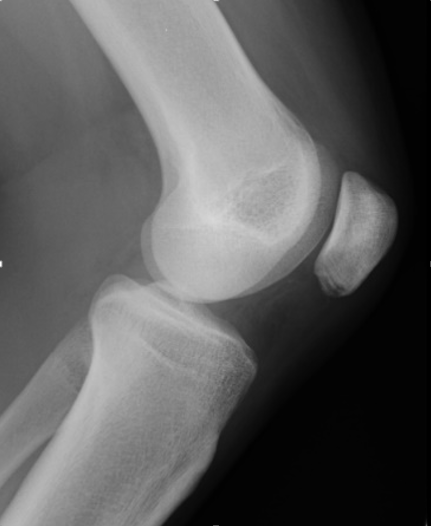

同部位を超音波エコーで観察してみました。健側(正常な膝)と比べると、ずいぶん腫脹しているのがわかると思います。

また、痛みが現れてから時間が経過しているためか、腱の部分だけではなく膝蓋骨にも不整な変化が見られます。

この症例の場合、膝蓋腱の深層における変化がとらえられます。